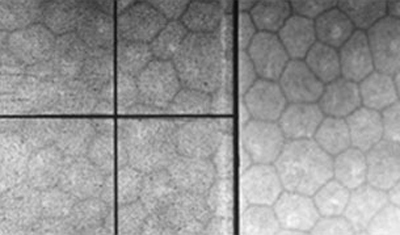

Siendo la capa más interna de la córnea, está en contacto con el humor acuoso y forma la pared de la cámara anterior; Está compuesta por células hexagonales distribuídas en una sola capa con una cantidad promedio de 2.500-3.000 células por mm2. Van disminuyendo con la edad. Permite el paso de nutrientes al interior de la córnea y controla su estado de deshidratación, siendo por lo tanto la capa responsable de mantener la transparencia corneal. El endotelio tiene muy escasa capacidad de regenerarse por lo que no es capaz de reparar por división un defecto en su extensión, lo cual hace agrandando y extendiendo sus celulas.

Endoteliografía